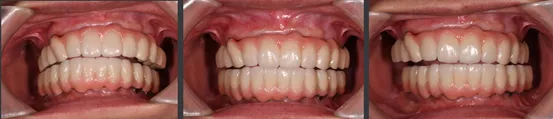

治疗后

即刻修复后患者的正侧貌美学评估:

正貌美学评估:

· 面部对称、三等分,面中线与中切牙中线一致,上下唇可自然闭合。

· 侧貌美学评估:

· 上唇丰满度:适中,鼻唇角105°,上下唇位于美学E线,直面型。

· 预告面型及修复后与修复前对比,患者的正侧貌美学得到了极大的改善,凸面型变为直面型。

· 修复体红白美学满意,前伸侧方咬合均无干扰,前牙前突问题解决,指导患者清洁。